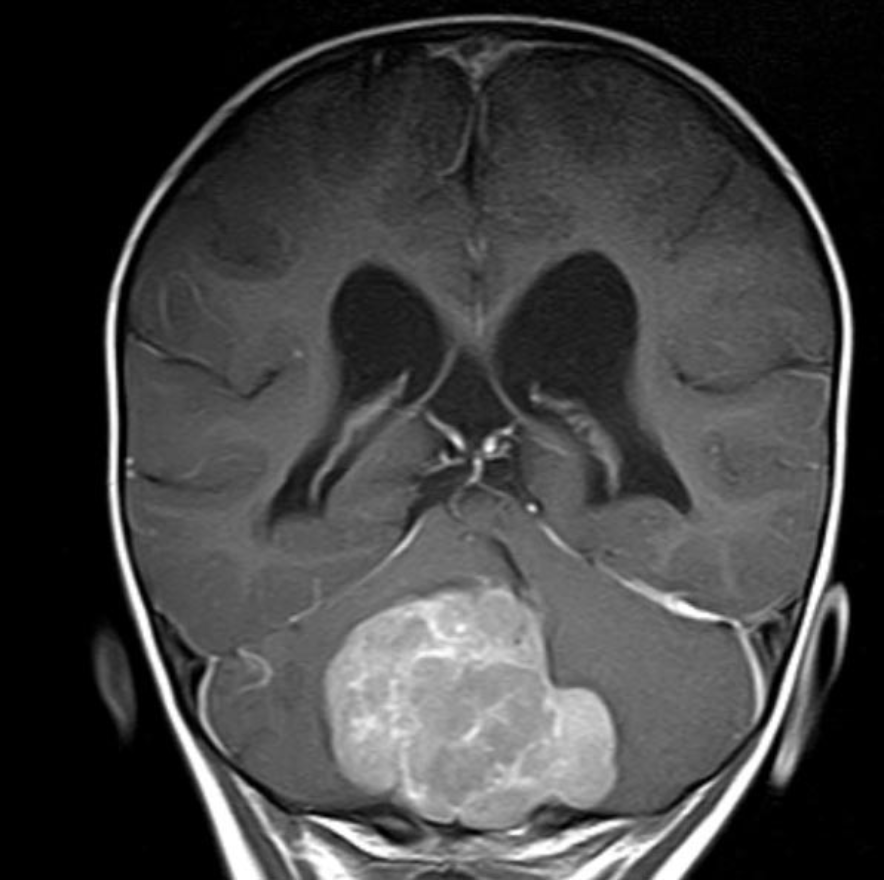

Medulloblastoma are among the most common solid tumors in children and the most common malignant brain tumor in children. The tumor grows in the cerebellum and can damage vital brain centers as it grows.

A certain type of medulloblastoma, which is characterized by its good chances of recovery and at the same time by the special structural properties of its tissue, served as a model for them: in so-called medulloblastoma with extensive nodularity (MBEN), small tissue chambers are delimited within the tumor, which are connected in a grape-like manner. The study showed that tumor cells located in these nodules were no longer actively dividing and their genetic program was similar to that of mature brain cells. In the intermediate areas, however, the scientists identified different cell types: In addition to immune and connective tissue cells, there were also significantly more aggressive tumor cells that continued to divide uncontrollably and whose genetic program was more similar to those of fast-growing medulloblastomas and immature nerve cells. In the course of their migration into the nodes, however, the cancer cells matured back into nerve-like cells and no longer divided.

MRI image: In so-called medulloblastoma with extensive nodularity (MBEN), small tissue chambers are delimited within the tumor and are connected in a grape-like manner.